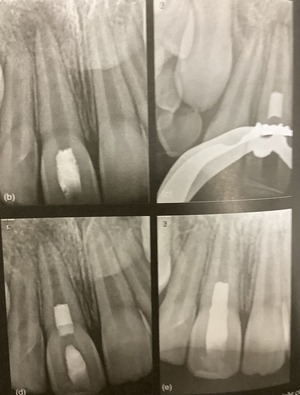

根管治療を始める前に、仮に詰めたり仮歯が必要になるかも。

その方が後の治療が効果的になるからです。

その歯が根管治療後に被されるのか?

残っている歯の量と場所から、どんな方法になるのかを考えるのに有効です。

例えば細いヒビが見つかったりすると、その歯が長持ちしそうなのか?どんな被せ方が良いのかに関わってきます。